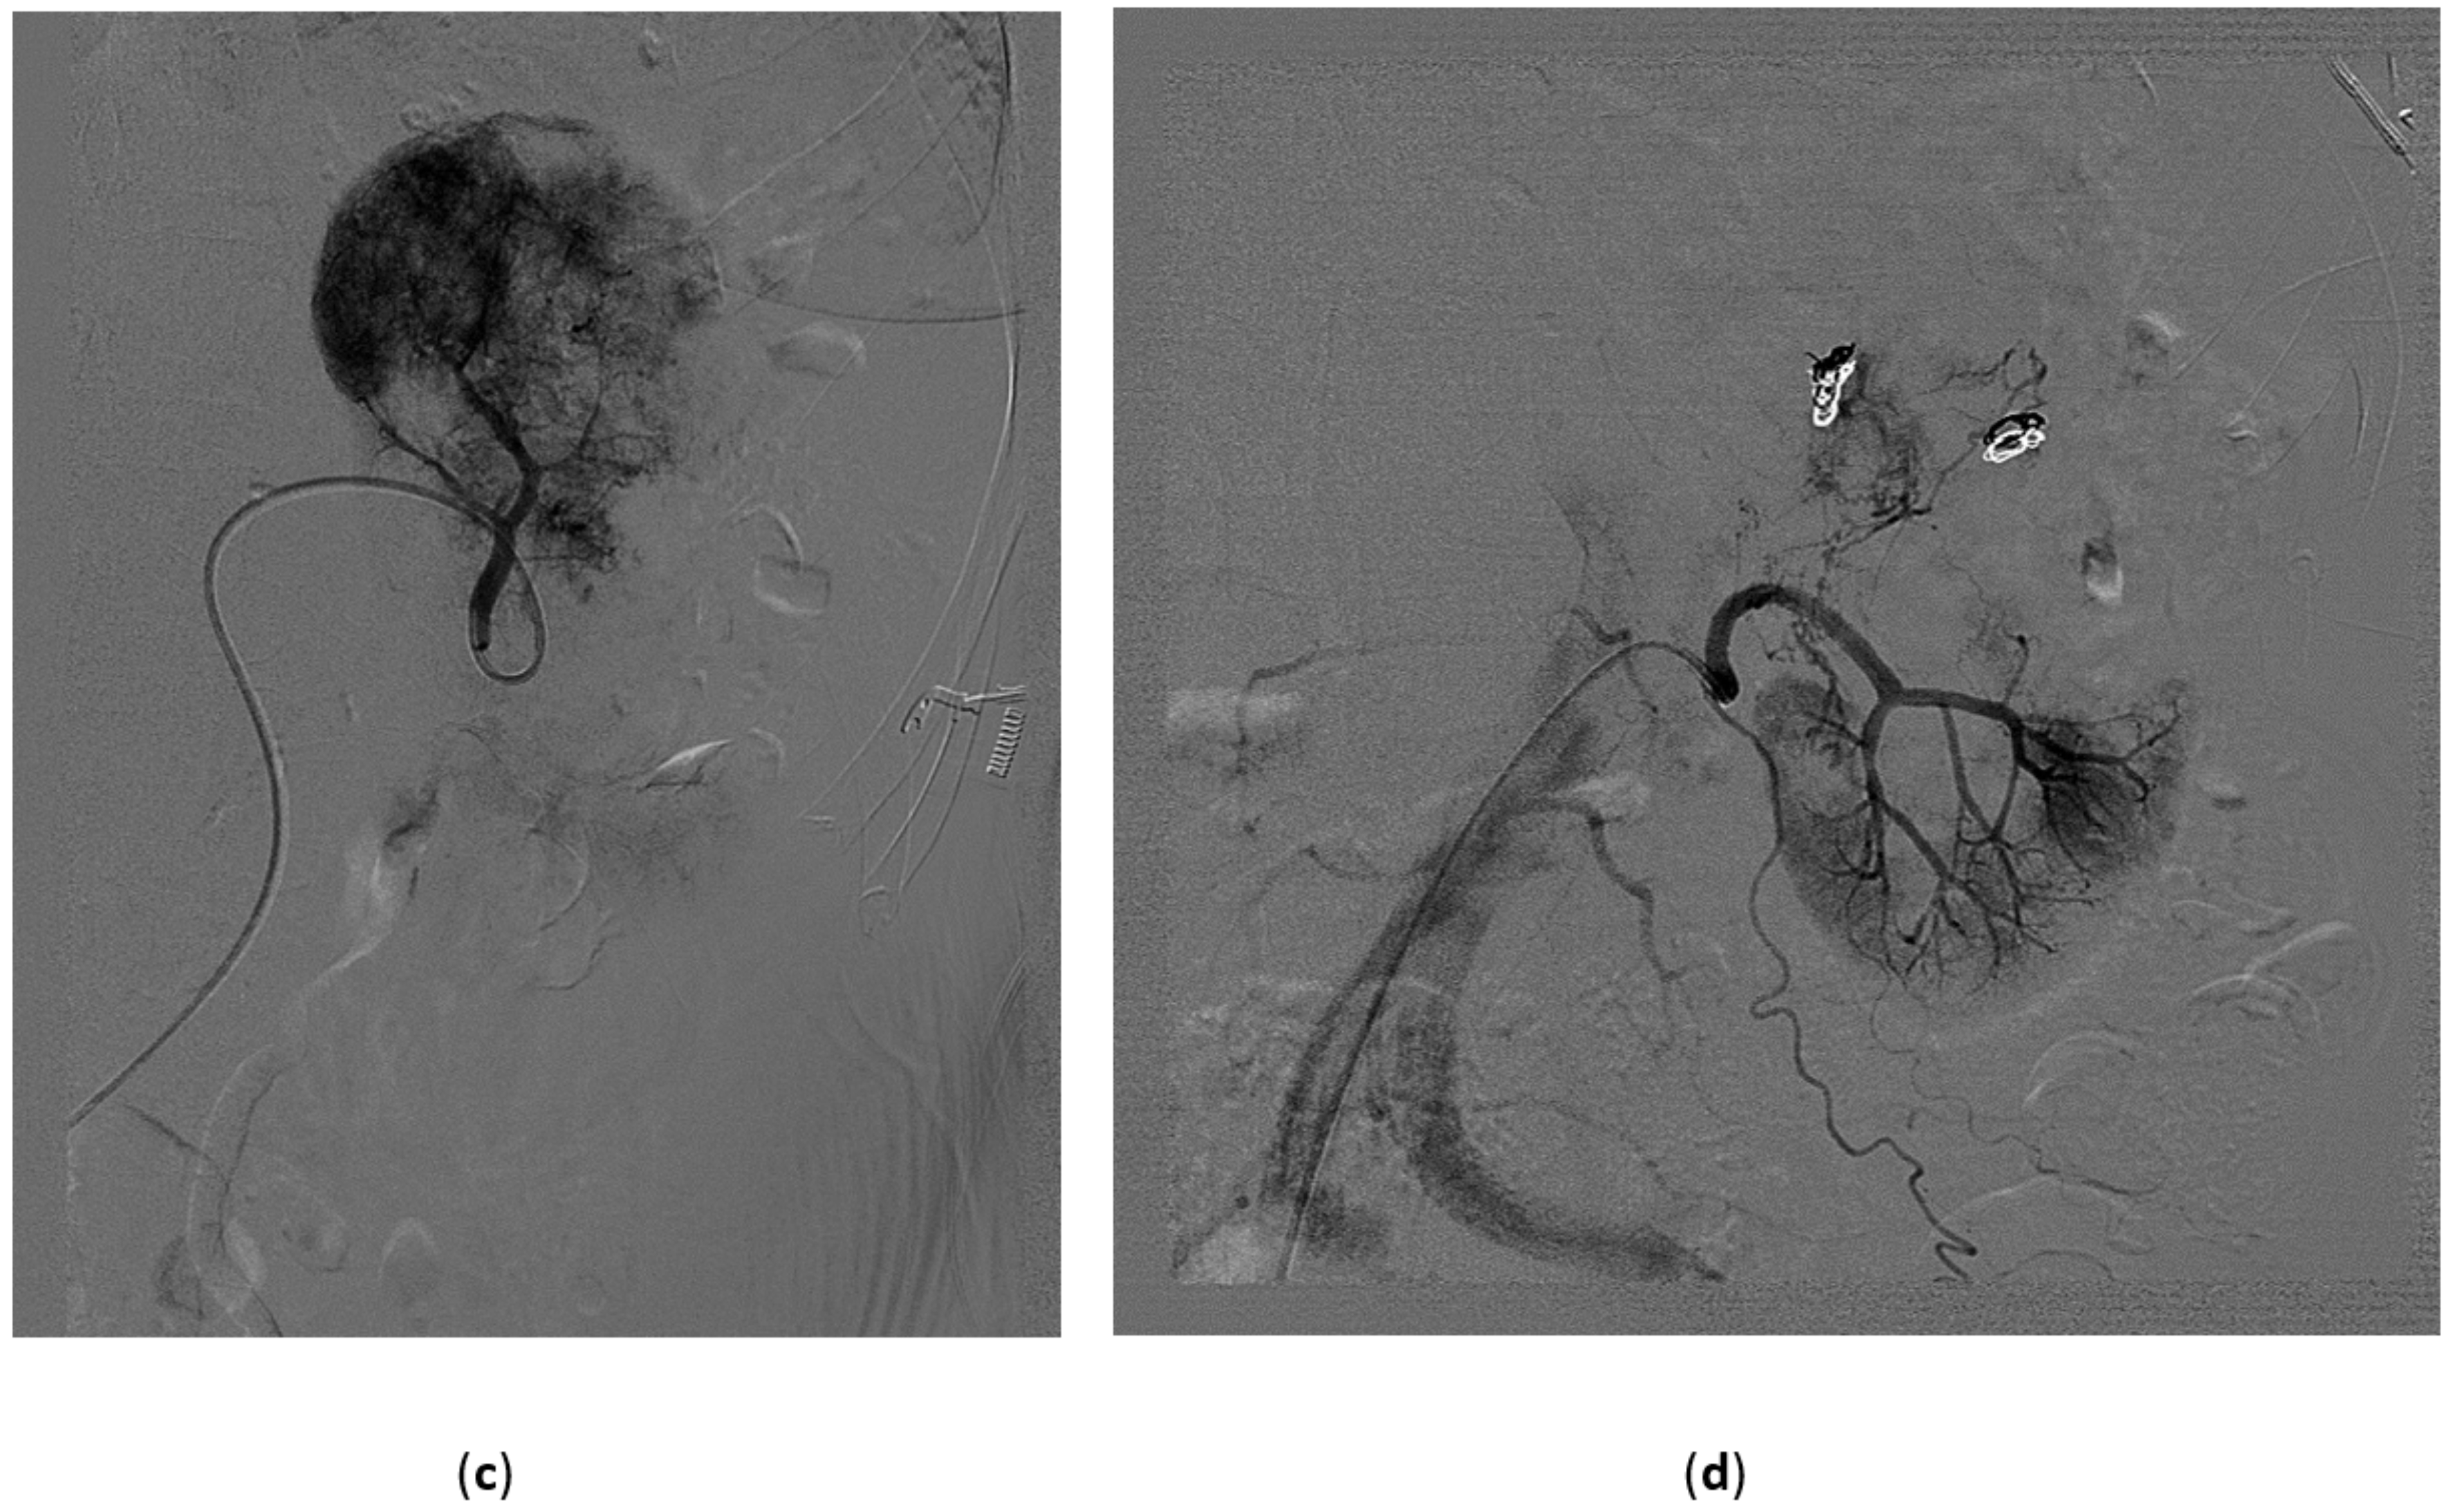

5.1. High-Flow Priapism

5.3. Treatment of High-Flow Priapism